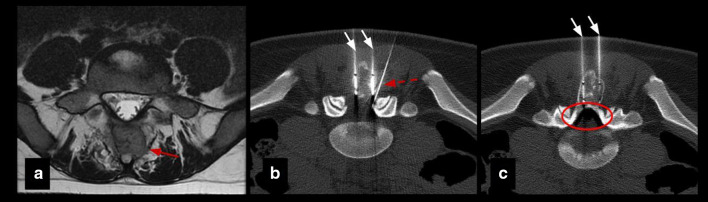

Fig. 2.

Insulation technique: epidural pneumo-dissection. Osteoblastoma in a 17-y.o patient. a Axial T2 MR image shows an expansile lesion in the posterior elements of L5 (red arrow). b, c Axial CT images show cryoprobes (white arrows) and epidural needle (dashed arrow) for pneumo-dissection system (circle) used to protect L4 and L5 nerve roots